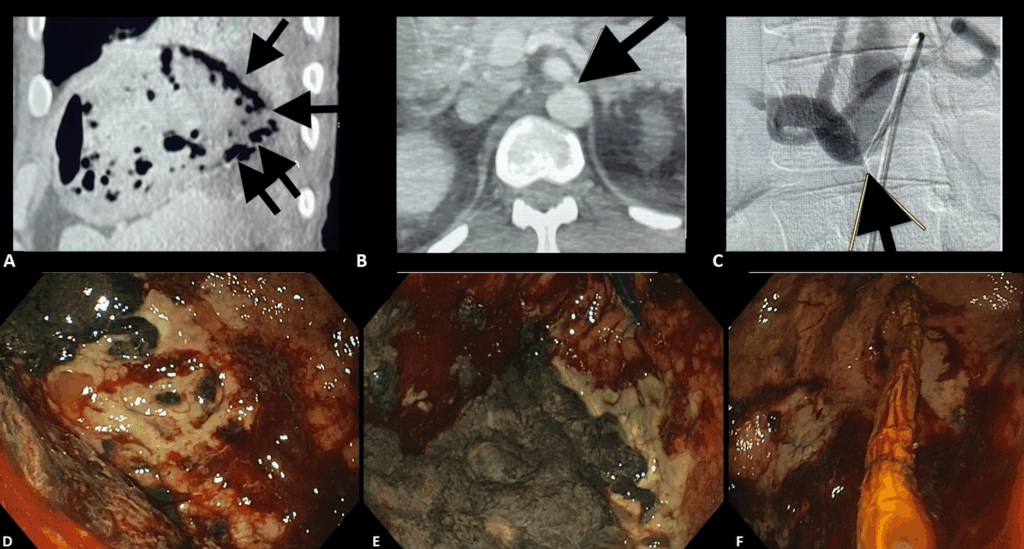

- La tomografía computarizada reveló neumatosis gástrica sin perforación (figura 1);

- La arteriografía mostró estenosis del tronco celíaco, compatible con síndrome del ligamento arcuato medio (figura 1), justificando isquemia gástrica.

Figura 2. Adaptado de Dall’Agnol et al. (9):

A: Tomografía abdominal que muestra neumatosis de la pared gástrica (flechas).

B: Angiografía por TC que muestra estenosis del tronco celíaco (flecha).

C: Arteriografía que confirma la estenosis del tronco celíaco (flecha).

D: Ulceraciones extensas y tejido necrótico con sangrado difuso en el cuerpo gástrico.

E: Tejido necrótico extenso en el fundus gástrico.

F: Paso del tubo de terapia endoscópica de vacío (1.ª sesión).